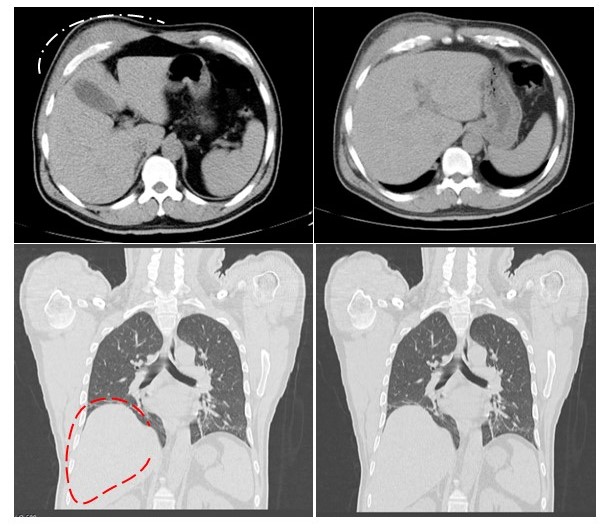

Se solicitó TC de tórax de alta resolución hallazgos: se describe la presencia de una lesión hipodensa, homogénea torácica pélvica de unos 100 mm x 110 mm de diámetros transverso y anteroposterior, que se ubica a nivel de la pared antero lateral del hemitórax derecho inferior, que parecía depender del músculo oblicuo externo derecho, que no compromete plano óseo, ni intravisceral. Conclusión: lesión sólida de pared torácica anterior lateral derecha (Figura 3).